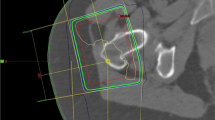

All patients received three-dimensional (3D) treatment planning. Planning CT scans were done with 5 mm slice distance (Siemens, Nürnberg, Germany) in the supine position. Delineation and planning were performed with routine software (Focal contouring®, XIO® treatment-planning [ELEKTA]). As clinical target volume, the region of the affected trochanter and the femur was delineated, according to the respective consultant. A safety margin of 1.5 cm in all directions was added to create the planning target volume. Of the plans 85% were done with a predominant anterior–posterior/posterior–anterior field technique. The other plans received further fields from lateral gantry positions.

a Location of several bursae in a planning CT scan of the right hip at apex of the greater trochanter. The gluteus maximus muscle is depicted in red, the gluteus medius in light green, and the gluteus minimus muscle in dark blue (more medial the iliopsoas muscle, also in dark blue). In bluish green, the fascia lata is delineated. In light purple the “deep bursa” is marked, in red the “anterior subgluteus medius bursa”, in light blue the “posterior subgluteus medius bursa”, and in yellow the “subgluteus minimus bursa”. b CT slice 0.6 cm more distal than in a. In addition to the structures in a, the “secondary deep bursa” is depicted in cyan (*). Please note the dorsal location of this bursa. c CT slice 2 cm more distal than in a. The gluteus maximus muscle is depicted in red, the iliopsoas muscle in dark blue. In bluish green, the fascia lata is delineated. The location of the “gluteofemoral bursa” is marked in brown (+)

Concerning these studies, the German guideline for radiotherapy of nonmalignant disorders recommends that “the superficial and deep, primary and secondary bursae of the gluteus maximus region” be included into the PTV [14]. Especially the distal localization of the gluteofemoral bursa is highlighted, as there is a high risk of missing its caudal edge.

Still, our own data seem to support the above-mentioned recommendations. The inclusion of the entire femoral neck circumference reflects a generous inclusion especially of the more dorsally located secondary deep subgluteus maximus bursa and the gluteofemoral bursa, both associated with the gluteus maximus muscle and tendons (Fig. 3b and c). The coverage of these bursae was significantly associated with treatment success 3 months after LD-EBRT in our patients in comparison with the treatment of only the lateral aspect of the femoral neck and the corresponding soft tissue mantle.

As the deep bursa and the superficial subgluteus maximus bursa are located in close anatomical relation to the bursae of the gluteus medius and minimus tendons, and due to the anterior–posterior/posterior–anterior treatment planning technique, the medius, and minimus bursae will receive a sufficient dose in daily clinical practice. Taken together, our data partially support the field definition recommendations by the above cited German guidelines [14].

We investigated other, quite simply measured factors associated with field definition like distances between field borders and the greater trochanter, the minor trochanter, the socket edge, or inclusion of the entire femoral head into the PTV. Only the latter was predictive of treatment response at the end of the LD-EBRT series in univariate analysis. However, there is no convincing explanation for this result, as the bursae are not anatomically linked to the femoral head. The only explanation (besides a random effect) is that some patients in our collective also suffered from coxarthrosis—without being identified in anamnesis, clinical examination, or imaging. This is why we do not recommend to include the entire femoral head into the treatment volumes unless this result is confirmed in other studies.